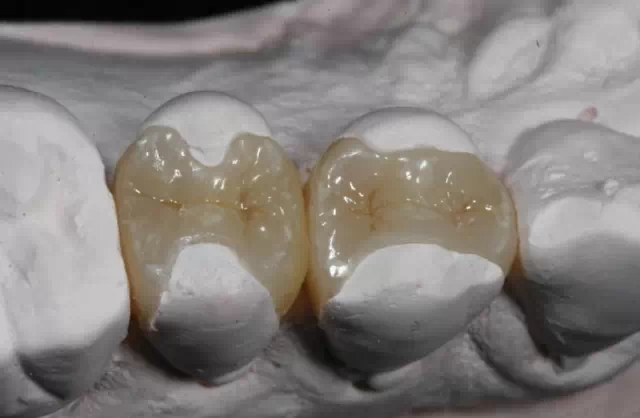

嵌體(ti) 和傳(chuan) 統的補牙不同之處是,嵌體(ti) 是在口外石膏模型上由專(zhuan) 門的牙科技師製作出來的,然後再由臨(lin) 床醫生將其戴入**口內(nei) ,粘固形成的。

嵌體(ti) 的優(you) 點就在於(yu) ,它的整個(ge) 的製作過程中完全避免了在口腔內(nei) 部操作的幹擾因素。這就使得嵌體(ti) 的製作比傳(chuan) 統的補牙要更精細。技師在製作嵌體(ti) 的時候,會(hui) 控製它與(yu) 牙體(ti) 的彌合程度,這樣就盡可能的避免了牙齒在日後的使用中再次出現齲壞。

嵌體(ti) 的另一個(ge) 優(you) 點是,因為(wei) 它的整個(ge) 製作過程是在口外完成的,所以它還可以很好的恢複原來牙齒的外形,恢複原來牙齒的咀嚼效率。而這一點,是傳(chuan) 統補牙無論如何都無法比擬的